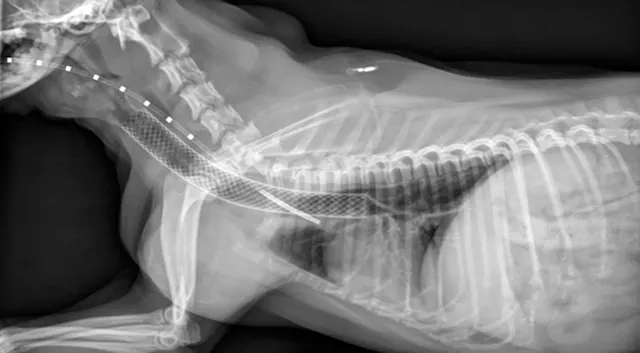

Preferred stent size is estimated from survey radiographs taken with the patient under general anesthesia. A probe marked with radiopaque lines at 1-cm increments is placed within the esophagus to permit correction associated with potential magnification. The endotracheal tube is retracted to where the cuff is inflated within both the cricoid and thyroid cartilages, and the trachea is expanded with positive pressure to determine maximal lumen diameter. Length is measured from the caudal surface of the cricoid cartilage to the cranial edge of the carina. Tracheobronchoscopy can be used to recheck the length of the trachea, determine the grade of collapse, and obtain samples for culture and cytology.

Stent selection is based on matching the desired stent diameter and length with measurements in the manufacturer’s foreshortening chart, which provides an estimate of final length based on the predicted diameter of expansion. The stent should span from just caudal to the cricoid cartilage to just cranial to the tracheal bifurcation. Final stent width should exceed the maximal diameter of the trachea by 10% to 20% to prevent stent migration.

Figure 1. Stent placement guided by tracheobronchosopy; the tracheal lumen is viewed with a rigid scope. Anesthesia is maintained with constant rate infusion, and oxygen is delivered into the trachea through a red rubber catheter.